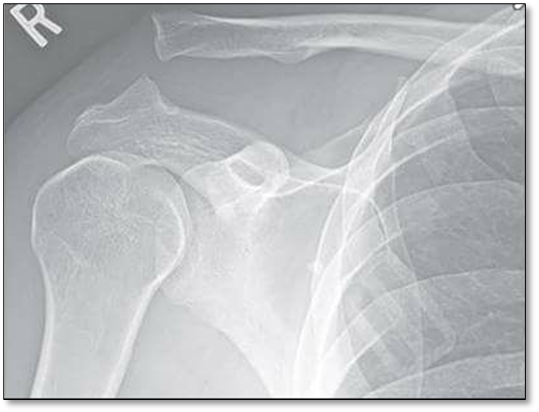

Hình ảnh trật khớp trên Xquang